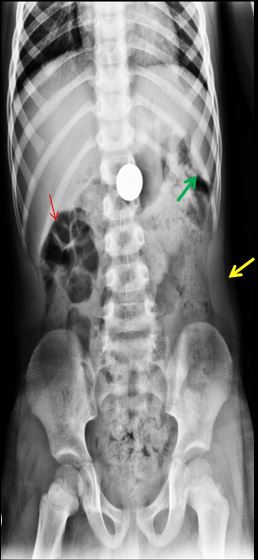

IDENTIFIQUE AS SETAS E DIGA PQ SÃO ADULTOS

SETAS AZUIS – NÁDEGAS DE UMA SENHORA OBESA

SETAS VERMELHAS – POLO CEFÁLICO DE UM FETO.

SETA AMARELA – CONTORNO UTERINO . OBSERVE O DESLOCAMENTO DAS IMAGENS GASOSAS COLÔNICAS.

SÃO ADULTOS PORQUE JÁ OCORREU A FUSÃO DAS LINHAS DE CRESCIMENTO.